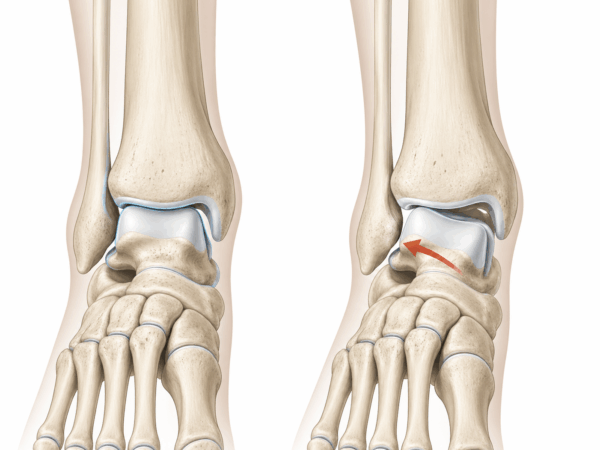

10年以上治らなかった足首の痛み。その正体は「外側荷重」と距骨のズレでした